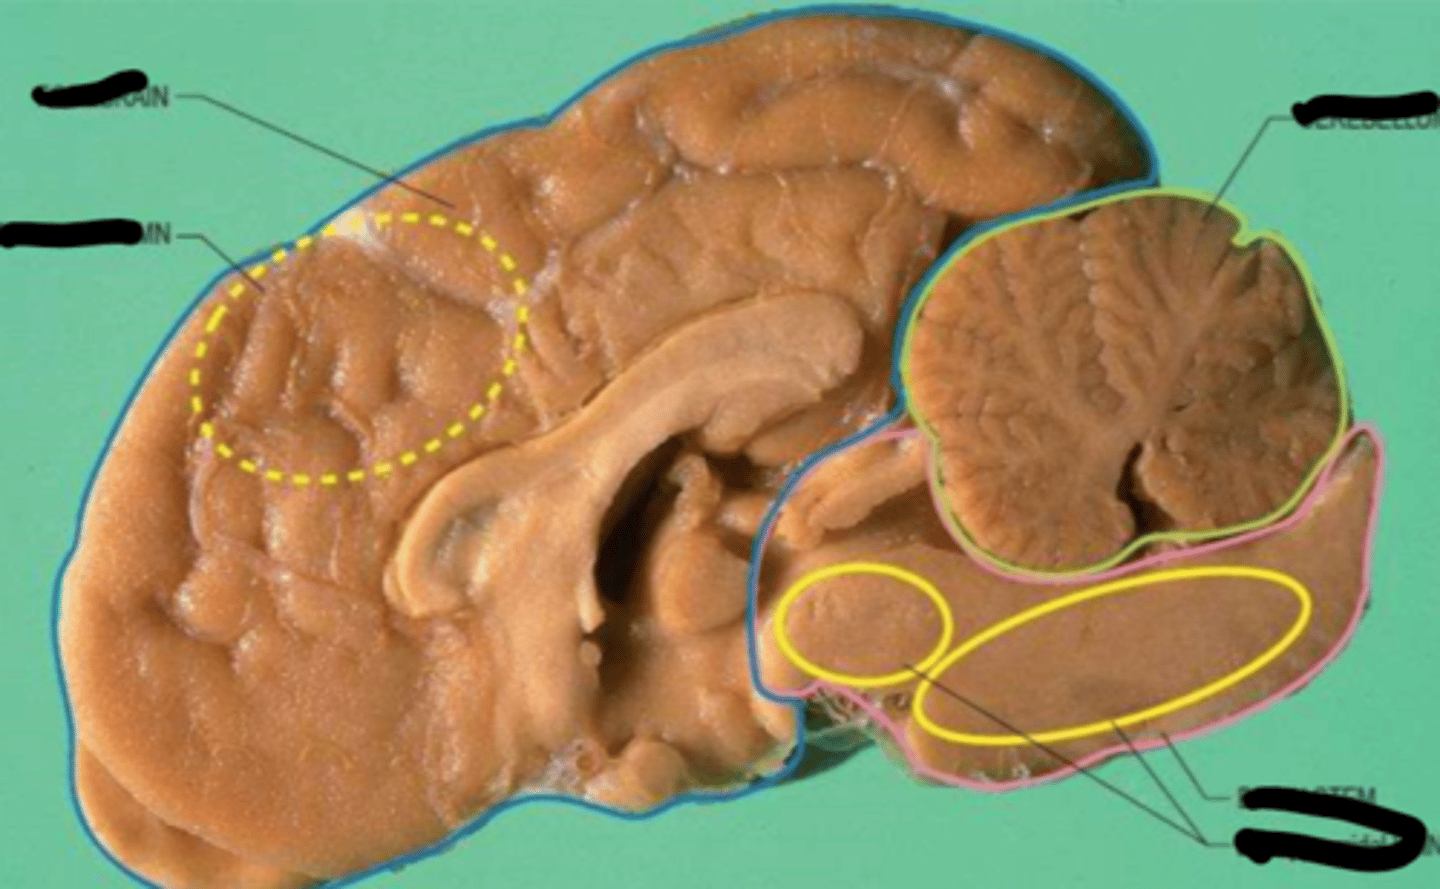

Components of the Basal Ganglia

Caudate nucleus

Putamen

Globus pallidus

Subthalamic nucleus (in diencephalon)

Substantia nigra (in midbrain)

Thalamus

Lenticular Nucleus

Consists of the putamen and globus pallidus

Striatum

Consists of the caudate nucleus and putamen

Main Circuit of the Basal Ganglia

Cerebral cortex -->

Striatum -->

Globus pallidus -->

Thalamus -->

Cerebral cortex